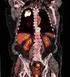

4 Diagnostische Möglichkeiten Angiografie (iadsa) früher Goldstandard CT-Angiografie optimale Darstellung der zentralen Abstromsituation Farbkodierte Duplexsonografie (FKDS) = heute Methode der 1. Wahl o nicht invasiv o wenig belastend für den Patienten o rasches Gewinnen von sehr komplexen Informationen durch Kombination von morphologischen und hämodynamischen Kriterien

- Henriette Lorenz